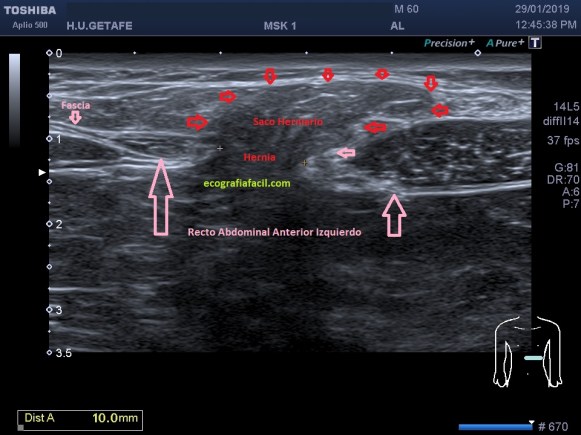

Vamos a partir de la normalidad y te vienes a ver ahora la patología que hoy nos ocupa, mira. En ocasiones podemos encontrarnos la imagen patológica que indica luxación del tendón, imagen 2. Es un corte en Eje corto. Ves la corredera bicipital vacía, el tendón fuera de su localización habitual, hacia medial, como es habitual, pero conservando la ecoestructura.

La imagen número 3 corresponde al corte en eje largo, mucho cuidado, siempre que tengamos el tendón del bíceps luxado, este se irá hacia medial, por eso, en eje largo vamos a encontrar la ecoestructura ligeramente hacia la axila, hacia medial.

Te lo digo siempre, mucho ojo con las estructuras tendinosas y la anisotropía, sobre todo la de este tendón que pese a estar luxado tiene su ecoarquitectura conservada, pero, en la imagen número 4 puedes ver la imagen del tendón con anisotropía en eje corto y te la pongo para que compares imagen 1 y 2 e imagen 4 y te des cuenta de cómo puede variar una estructura si no realizamos la técnica correctamente. Ojo con esto ya que podemos confundir a la radióloga a la hora de hacer el informe. Combatir la anisotropía es tarea exclusiva del operador